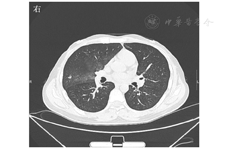

入院后体格检查:体温为39.8 ℃,呼吸为19次/min,脉搏为98次/min,血压为128/86 mmHg(1 mmHg=0.133 kPa)。一般情况尚可,眼眶、颞部明显凹陷,咽部充血,全身散在大面积红色斑丘疹及疱疹,部分破溃流脓,躯干、头面部明显,大部分已结痂,颈部及左腹股沟处可分别触及一枚0.5 cm×0.5 cm大小的淋巴结,可推动,无触痛,心、肺、腹部无特殊,双下肢无水肿,病理反射阴性。超声心动图检查示:心包少量积液。淋巴结超声检查示:双侧颈部、腹股沟区、腋窝淋巴结声像。胸部CT检查示:双肺弥漫粟粒结节及微小结节;右肺上叶后段、右肺中叶多发磨玻璃影。实验室检查:白细胞计数为2.72×109/L,中性粒细胞计数为1.92×109/L,淋巴细胞计数为0.52×109/L,白蛋白为27.2 g/L,ALT为79 U/L,AST为66 U/L,谷氨酰转肽酶为169 U/L;CRP为80.0 mg/L,降钙素原为1.07 μg/L;ESR为46 mm/1 h;HIV抗体及肿瘤标志物均为阴性;甲状腺功能及抗体正常;免疫球蛋白正常。血二氧化碳分压为34.3 mmHg,血氧饱和度为67.0%,提示低氧血症。多部位骨髓活组织检查提示:感染性骨髓象;淋巴结活组织检查结果未见异常。1,3-β-D-葡聚糖试验阴性,呼吸道合胞病毒IgM阳性;结核分枝杆菌检测阴性;肥达外斐试验阴性。CMV DNA阳性。入院第2天,患者手臂、腰部出现新发融合性充血性皮疹,血培养检出琼氏不动杆菌,宏基因组学第二代测序提示以α-疱疹病毒3型为主,予以莫西沙星0.4 g静脉滴注(1次/d),喷昔洛韦软膏外用,更昔洛韦0.5 g口服(3次/d),人血白蛋白支持治疗。入院后第2周至第3周,患者未再出现发热,全身酸痛缓解,全身疱疹及斑丘疹明显消退。9月23日夜间,患者体温突然骤升至39.5 ℃。复查胸部CT示:双肺多发弥漫粟粒结节及微小结节,左肺上叶前段、右肺上叶尖段、右肺下叶前基底段近右心房处新增多个结节状密度增高影,伴周围模糊影,左肺上叶尖后段小结节灶体积较前增大,考虑炎性改变,见图1。复查血培养阴性,痰培养阴性,连续2次复查1,3-β-D-葡聚糖试验结果分别为135.50 ng/L和165.5 ng/L。纤维支气管镜检查示:真菌及抗酸杆菌涂片阴性,肺泡灌洗液培养出奈瑟干燥球菌和草绿色链球菌生长。结合患者有4周糖皮质激素使用史、CD4+T淋巴细胞减少、1,3-β-D-葡聚糖试验阳性、临床表现和影像学检查,考虑合并肺部真菌感染。请临床药学部会诊后,给予伏立康唑,左氧氟沙星0.5 g静脉滴注(1次/d),治疗后患者体温逐渐恢复正常。10月2日复查胸部CT:双肺炎性病变较前吸收;心包少量积液已明显吸收。CD3+T淋巴细胞比例为0.444,CD4+T淋巴细胞比例为0.122,CD8+T淋巴细胞比例为0.426,CD4+T淋巴细胞计数为83/μL, CD8+T淋巴细胞计数为290/μL,CD4+/CD8+比值为0.28。2019年10月3日患者症状缓解出院,继续伏立康唑200 mg口服(2次/d),治疗8周。2019年11月10日和12月8日电话随访患者未再发热,无其他不适,复查胸部CT病灶已完全吸收,因经济困难拒绝进行淋巴细胞亚群检测。